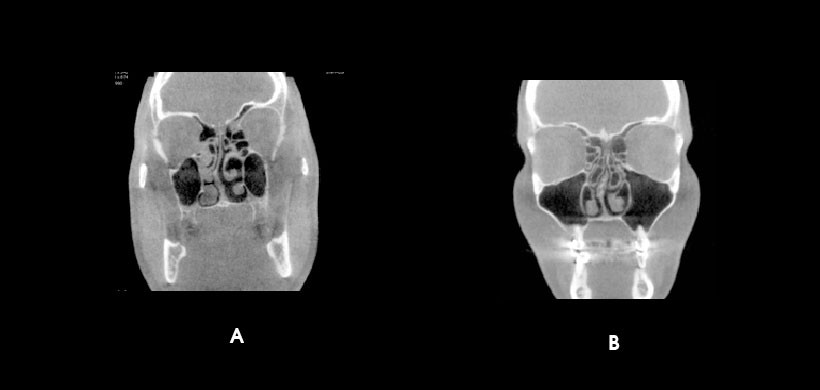

Fig 1. A, B. Variaciones del cornete medio, A) cornete medio invertido, con una desviación del tabique nasal hacia la derecha. B) cornete medio neumatizado bilateral asociado a desviación del tabique nasal hacia la derecha.